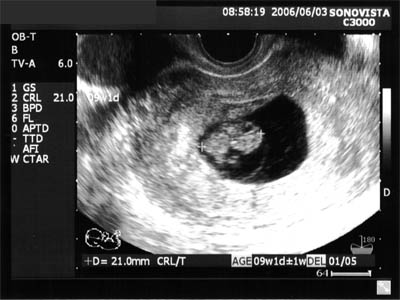

| 2006年5月6日(土) |

| 妊娠検査薬で陽性が出てから1週間、4w6dでの診察。 5.6mmの小さな胎嚢が確認できました。 |